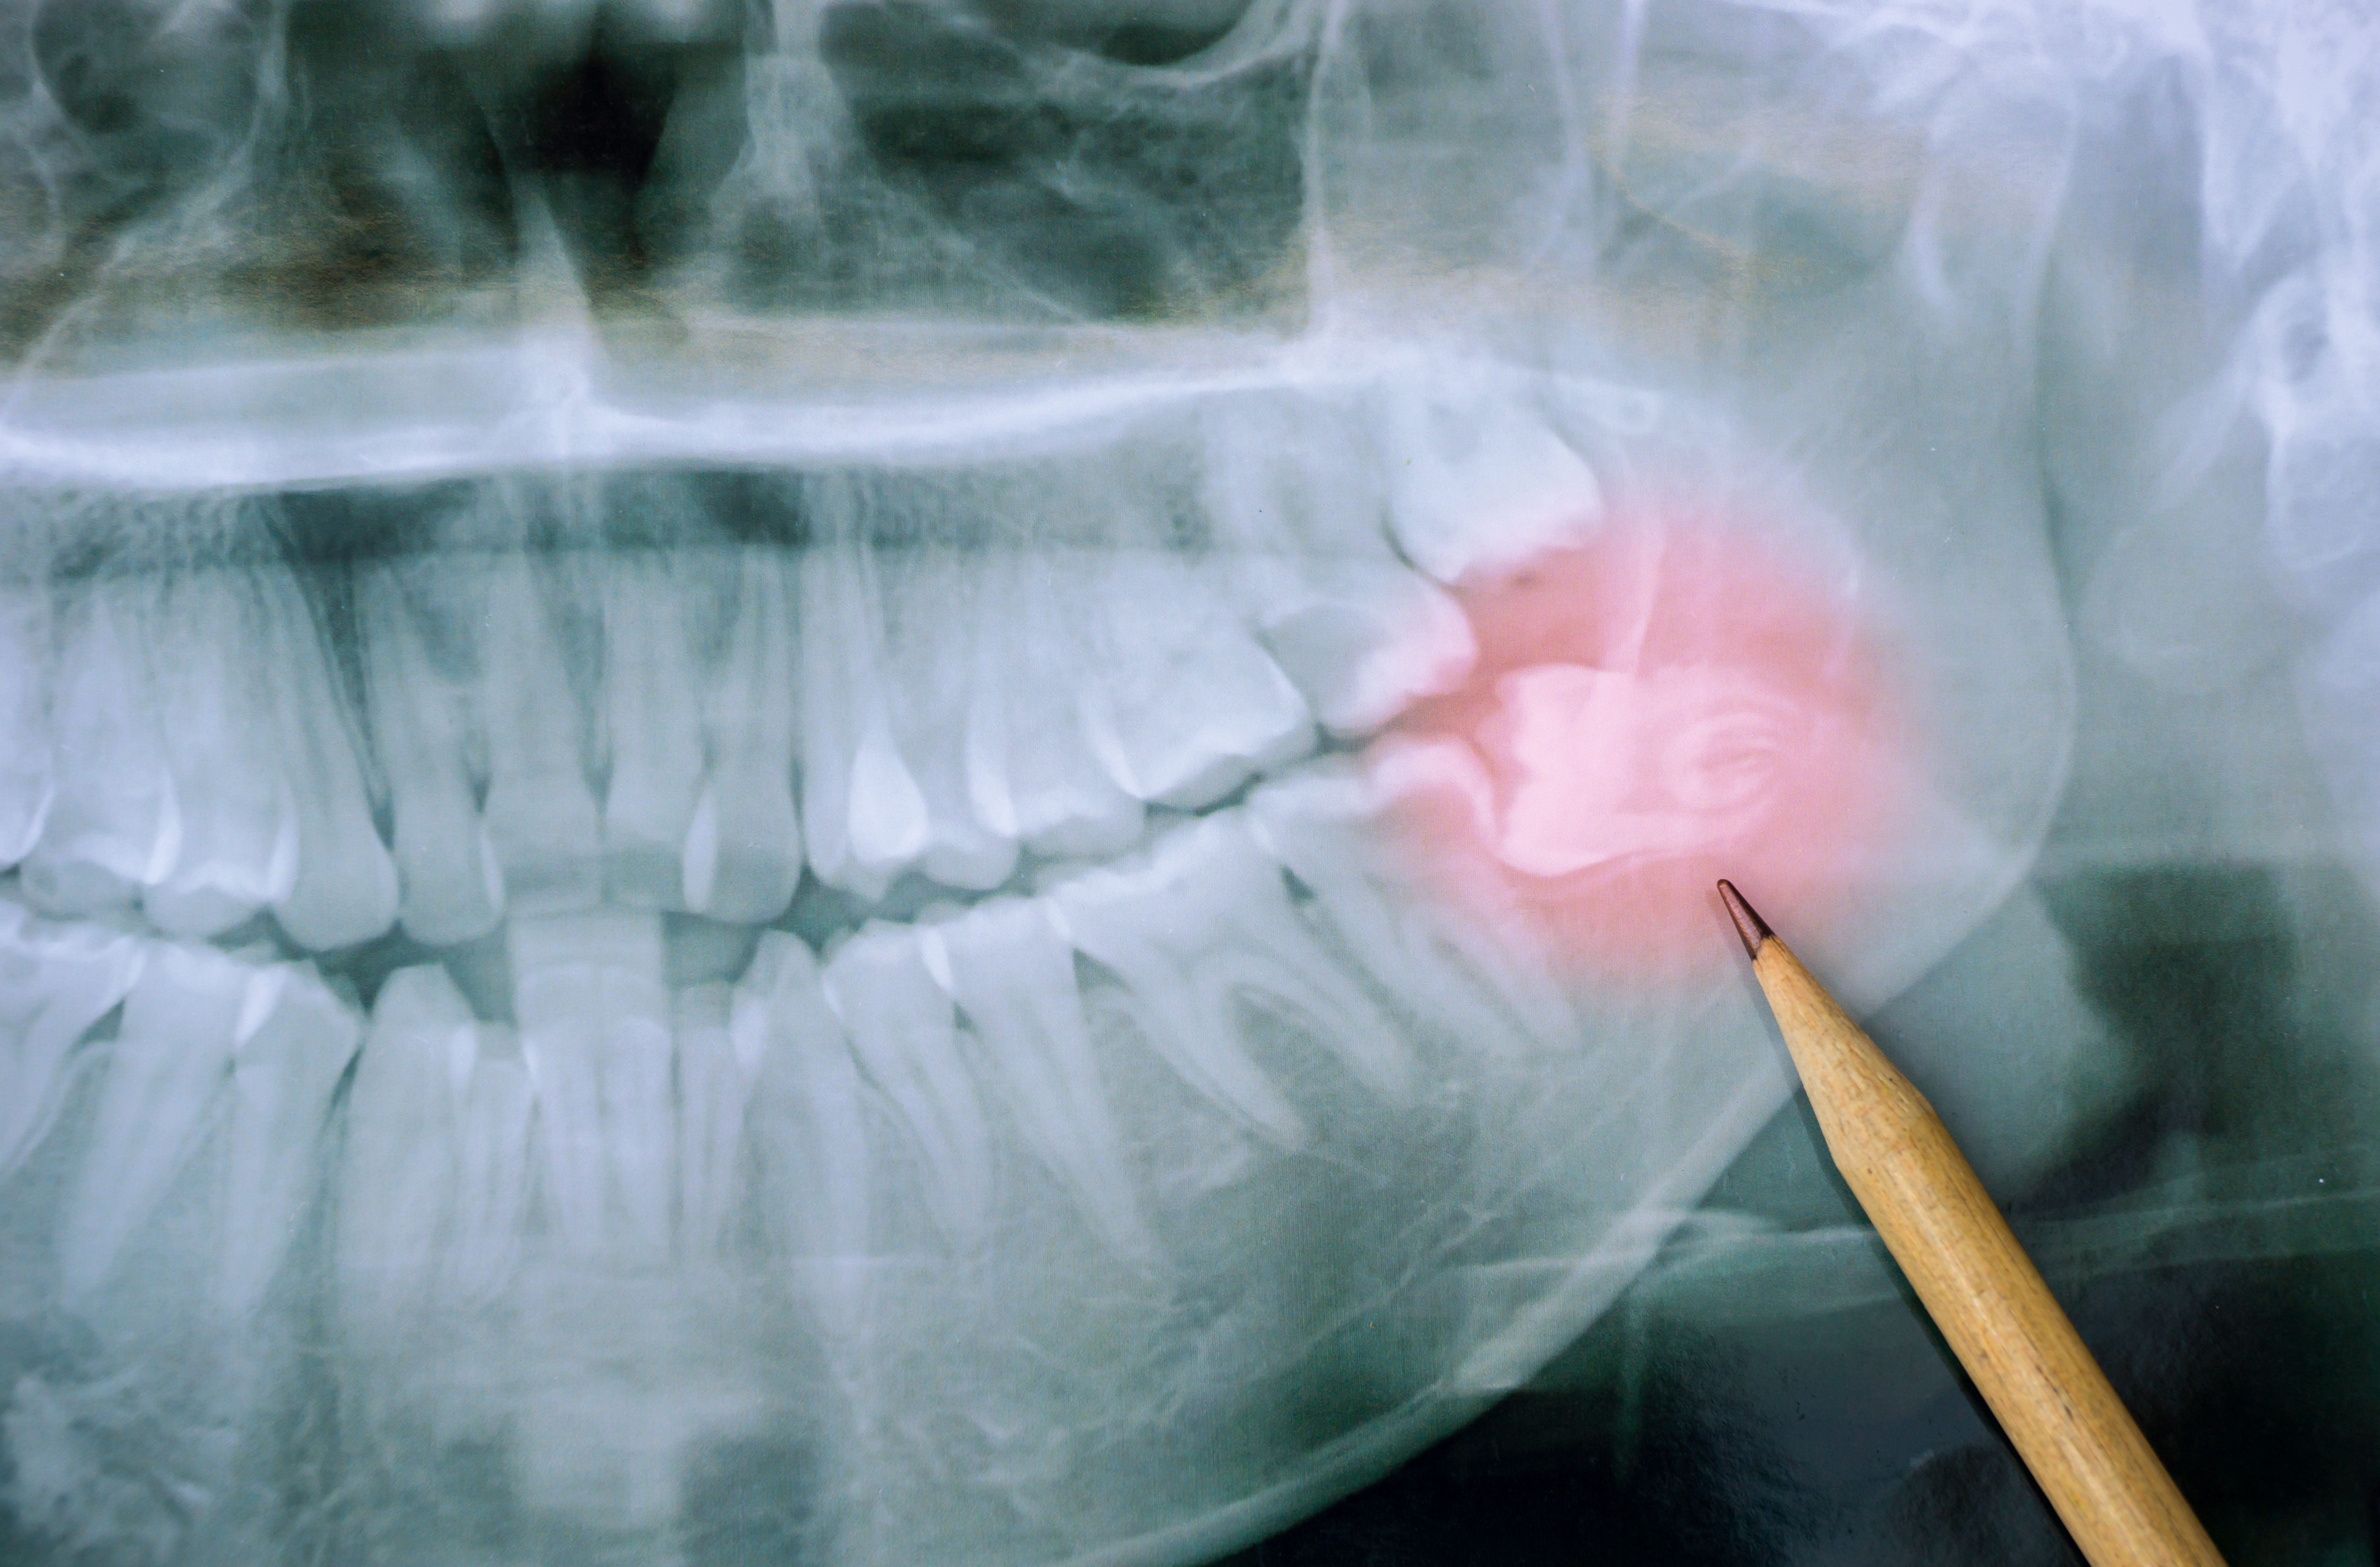

아래 사진에서 빨간 화살표로 표시한 흰 줄이 두 개 보이시죠?

아래턱을 지나가는 터널 같은 구조입니다.

이것을 하악관(Mandibular canal)이라고 합니다.

하악관은 계란껍질 만한 두께를 가진 벽이 있습니다.

이 하악관으로 입술, 아래턱의 피부, 잇몸의 감각을 담당하는 신경(하치조신경, Inferior alveolar nerve)이 지나갑니다.

그리고 치아와 아래턱에 혈액을 공급하는 큰 혈관도 지나가죠.